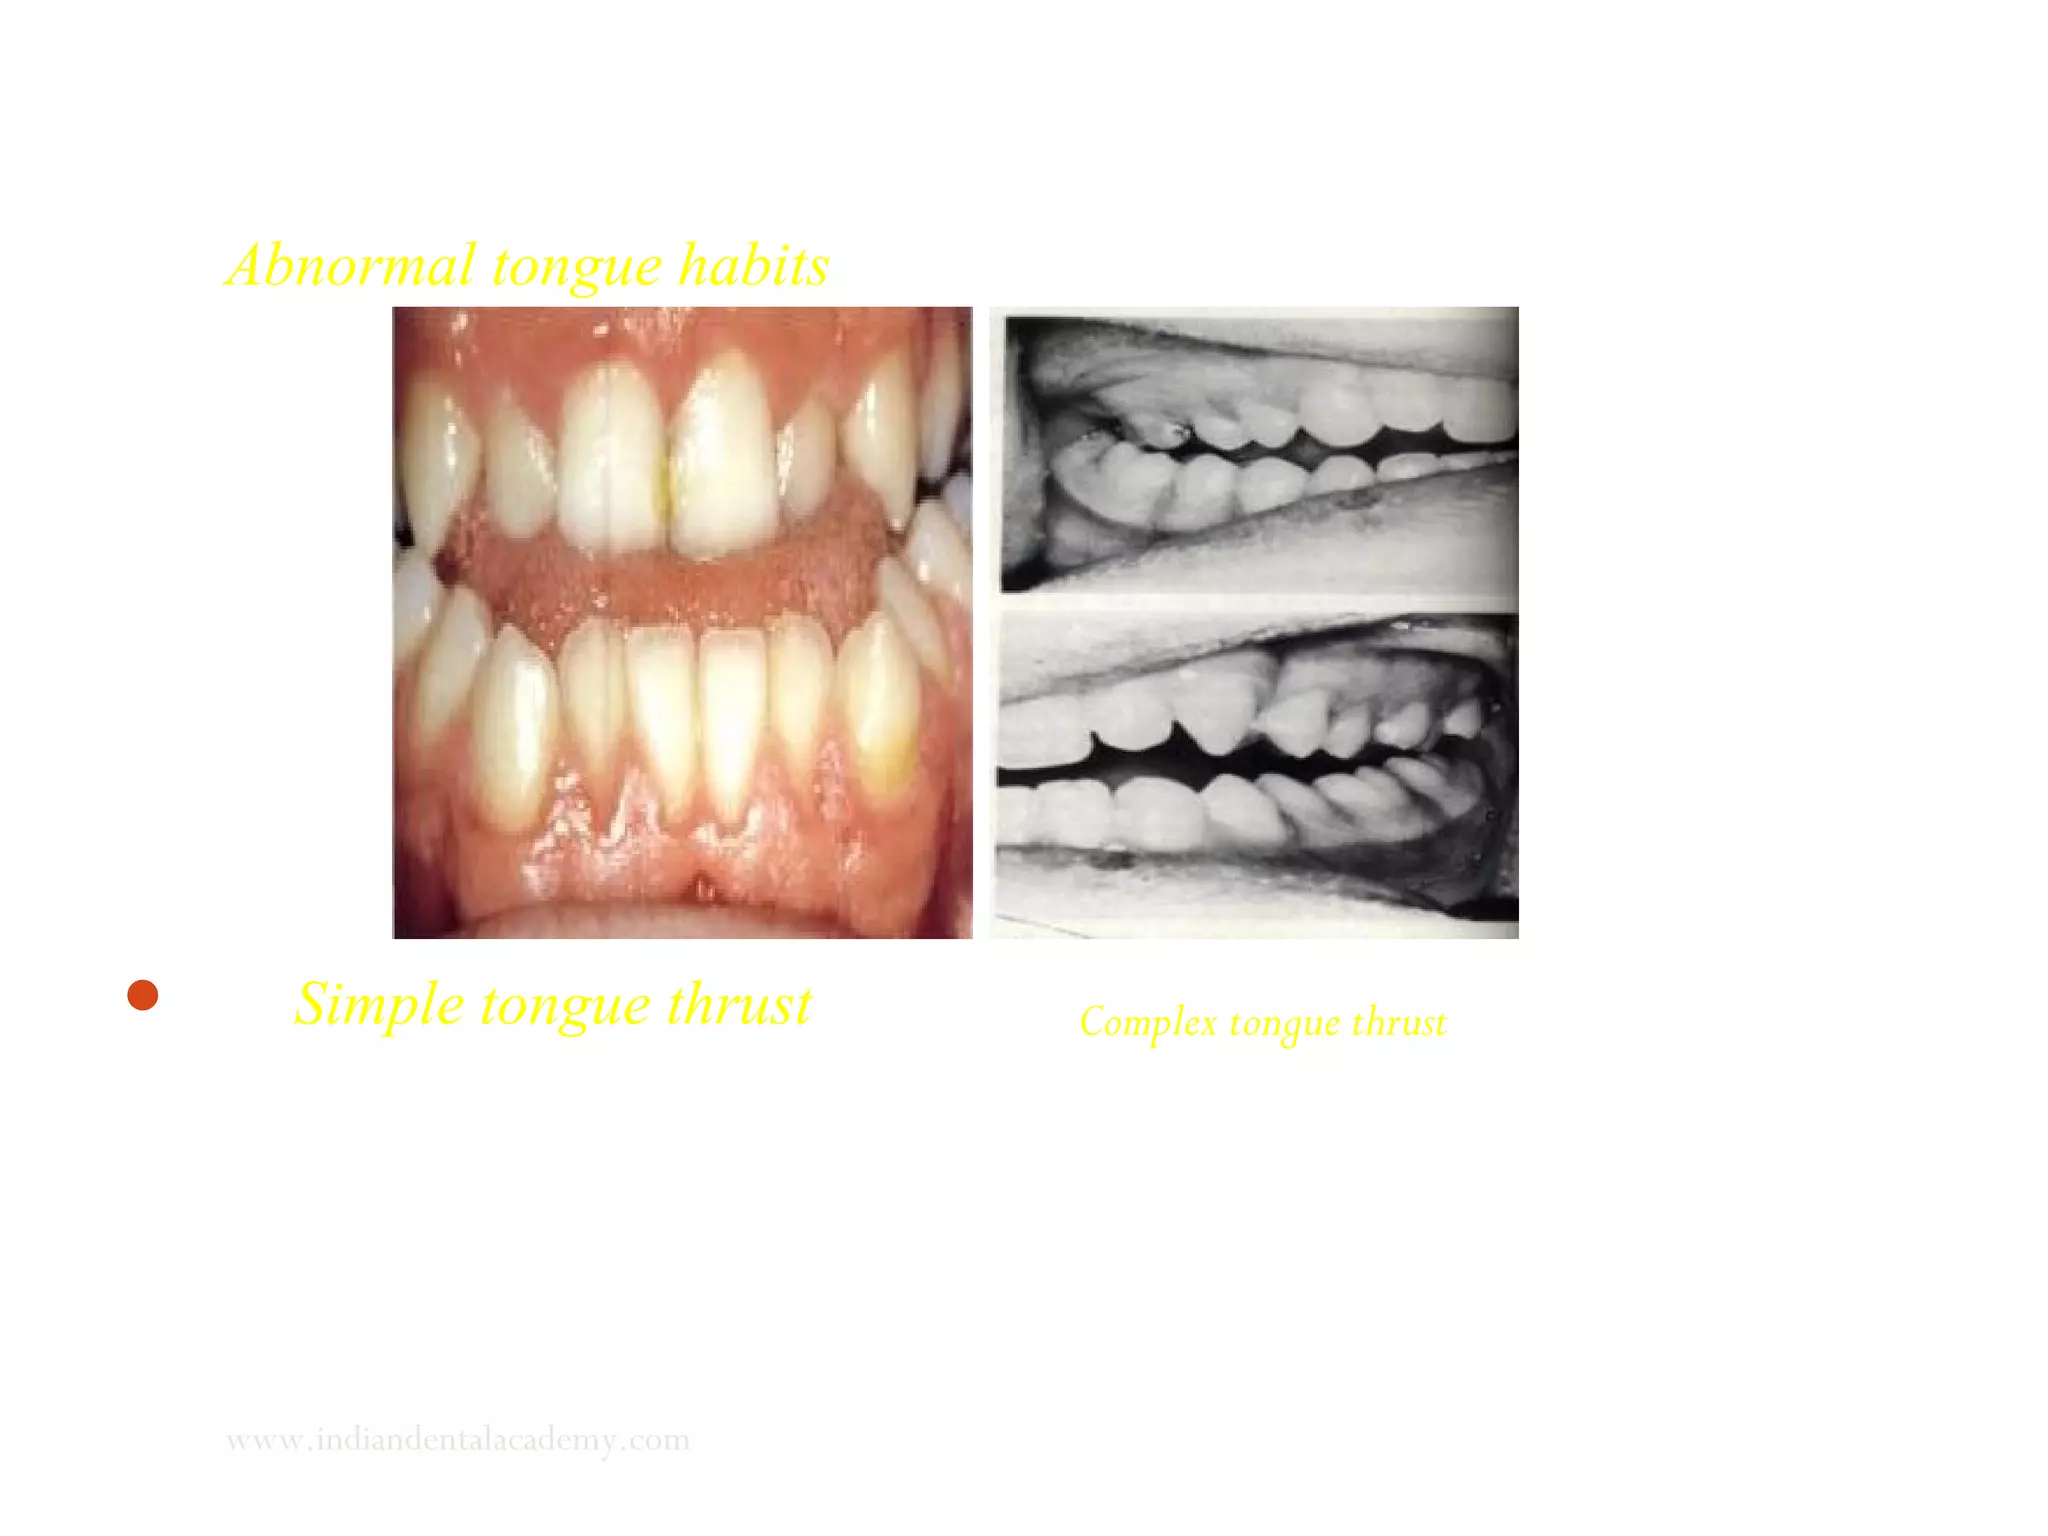

Abnormal tongue habits

 Simple tongue thrust Complex tongue thrust

Clinical significance of abnormal swallowing

1. Simple tongue thrust corrects itself with correction of the

open bite.

2. Complex tongue thrust requires occlusal stabilization by

orthodontic treatment followed by tongue training with

exercises.

3. Retained infantile swallow is a primitive reflex and correction

is difficult . Poor prognosis.

www.indiandentalacademy.com